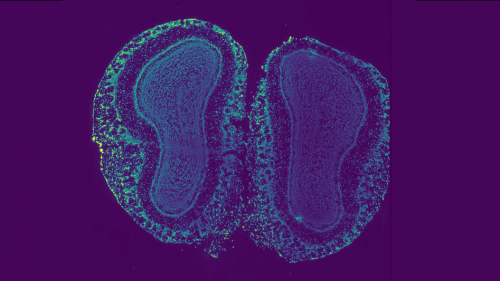

slice of tissue from a mouse olfactory bulb

A piece of tissue from the olfactory bulb of a mouse. Variations in color show variations in cell types and gene expression. Image courtesy of the researchers.

Using a new deep learning algorithm, researchers at Princeton have designed an approach to map the cellular organization of tissues by modeling spatial patterns in molecular data. This development has implications for advancing cancer treatment and understanding aging, development and other cellular processes.

The algorithm they created to do this uses deep learning, a kind of artificial intelligence, that reveals subtle variation in gene expression across tissues.